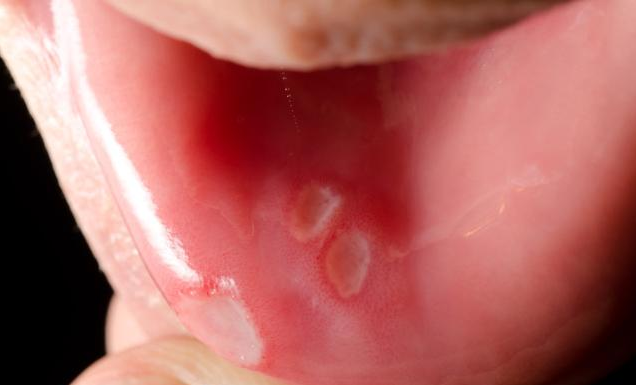

在坐月子期間,產(chǎn)婦由于飲食不當(dāng)或因體質(zhì)差,上火,很容易出現(xiàn)口腔潰瘍的情況,口腔潰瘍會(huì)影響產(chǎn)婦的食欲,不利于產(chǎn)后恢復(fù),那么,坐月子口腔潰瘍?cè)趺崔k呢?接下來(lái)八寶網(wǎng)小編就來(lái)說(shuō)一說(shuō)。

產(chǎn)后吃得多、動(dòng)得少,于是腸道蠕動(dòng)變緩了,食物在腸內(nèi)得不到正常的消化,吃下的食物在體內(nèi)就會(huì)越積越多,長(zhǎng)期沉積在腸道內(nèi)的食物不僅容易代謝產(chǎn)生毒素,還會(huì)積滯生熱,從而造成新媽咪出現(xiàn)口腔潰瘍、口腔異味等癥狀。

而且女性在坐月子期間容易出現(xiàn)上火,這時(shí)候體質(zhì)較差,很容易導(dǎo)致口腔潰瘍的情況。